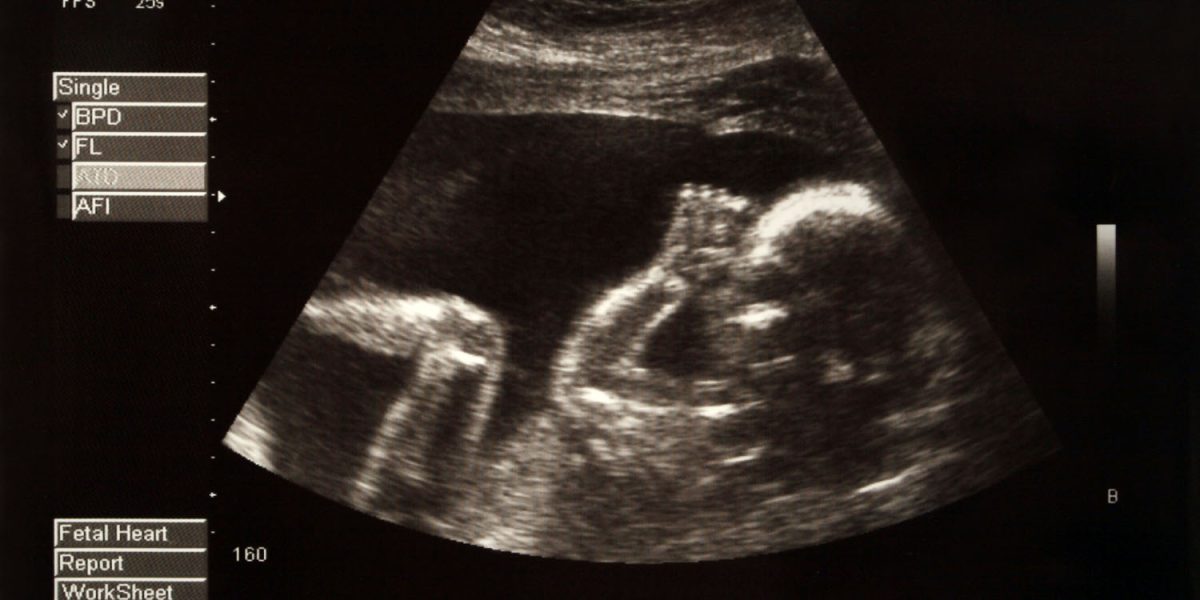

The study involved 190 expectant parents who visited an obstetrics and gynecology clinic, primarily during their routine 20-week pregnancy ultrasound. The average age of participants was around 31. Of those, 80% were married, while the remaining 20% were in a relationship.

Participants filled out a questionnaire regarding whom they thought the fetus resembled. They were given options like “Mother,” “Father,” “Relative of the mother,” “Relative of the father,” and “Does not look like anyone.”